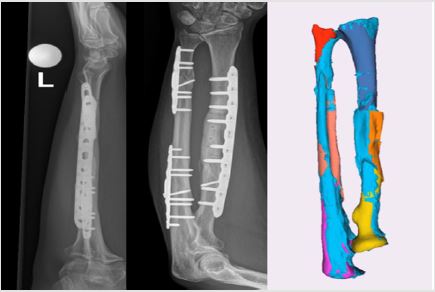

Follow-up

Figure 6: Anteroposterior and Lateral Radiographs (a) and (b). 3D Reconstruction (Light Blue) in Comparison with the Position of the Planning (Other Colors) at 4 Months.